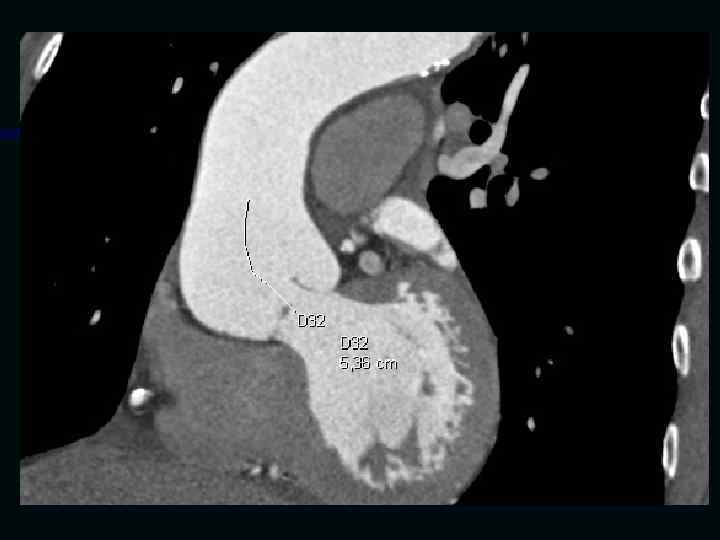

Исследование сосудов грудной клетки

Исследование сосудов брюшной полости